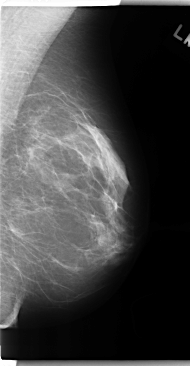

C_0149_1.RIGHT_CC

RIGHT_CC LINES 4744 PIXELS_PER_LINE 2592 BITS_PER_PIXEL 12 RESOLUTION 50 OVERLAY

FILE: C_0149_1.RIGHT_CC.OVERLAY

TOTAL_ABNORMALITIES 1

ABNORMALITY 1

LESION_TYPE MASS SHAPE OVAL MARGINS ILL_DEFINED

ASSESSMENT 4

SUBTLETY 1

PATHOLOGY MALIGNANT

TOTAL_OUTLINES 1

BOUNDARY